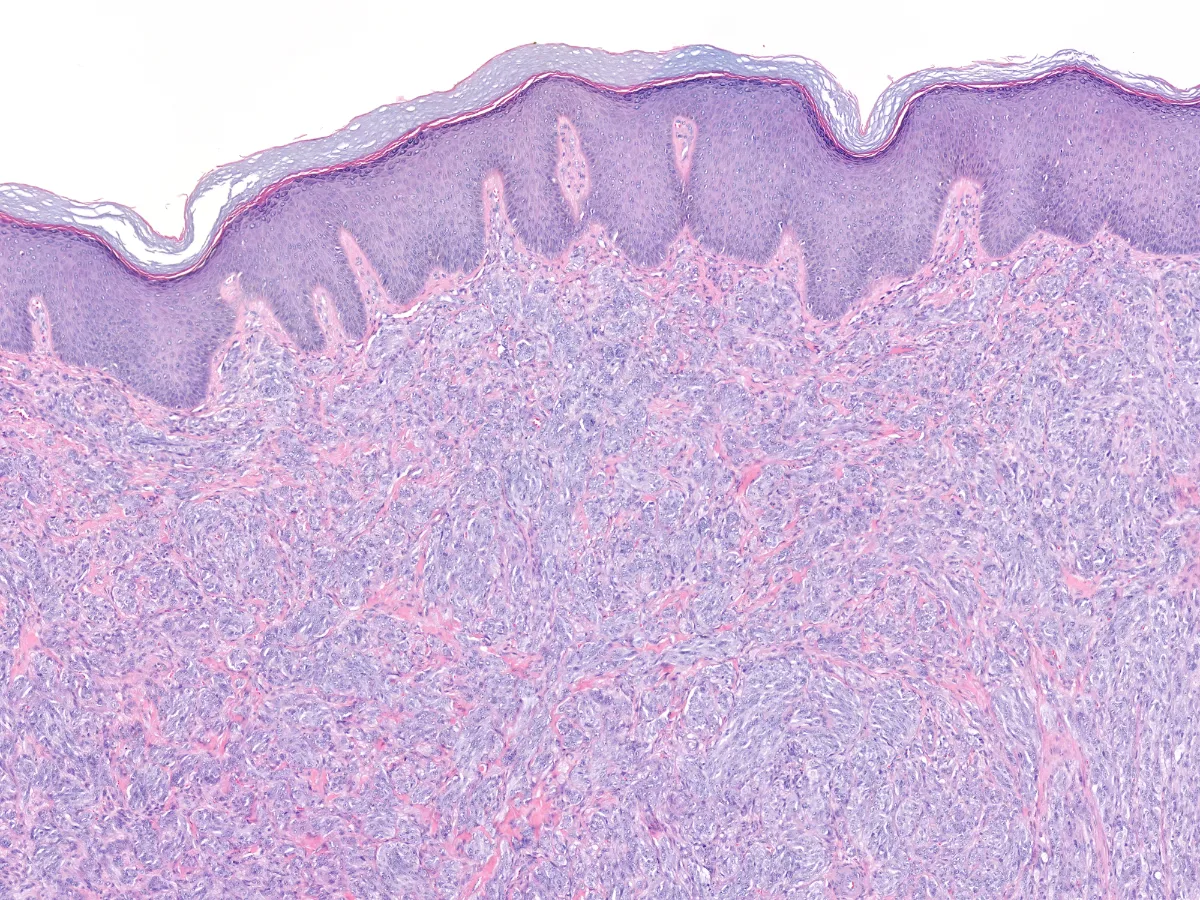

Los cortes histológicos muestran una tumoración dérmica bien delimitada, no encapsulada, que ocupa todo el espesor de la dermis reticular, constituida por células con cierto pleomorfismo, núcleos vesiculosos con nucleolo prominente y citoplasma anfófilo que se agrupan formando pequeños nidos bien delimitados y separados por finos tractos de colágeno. El índice mitótico es elevado (4 mitosis por mm2).

1. HE 2x

- La morfología es uniforme, con gran semejanza al sarcoma de células claras. Se tratan de tumores nodulares dérmicos bien circunscritos, no encapsulados y sin pigmento. Pueden apoyarse en la epidermis, aunque raramente la afectan. Las células se disponen en nidos y fascículos cortos y largos que se entrecruzan, así como bandas fibrosas delgadas entre estos haces. Las células son fusiformes con un amplio citoplasma de pálido a anfófilo, cromatina vesiculosa y nucleolo prominente. Pueden tener mitosis típicas. PMID: 35993578.